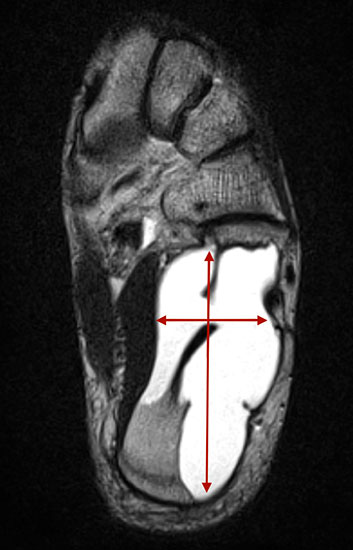

Die juvenile Knochenzyste (Syn. Solitäre Knochenzyste) findet sich am Fuß fast ausschließlich am Calcaneus im Bereich des Ward´schen Dreieckes bzw. im ventralen triangulären Bereich zwischen den Haupttrabekelgruppen (Diard´s Area 6) 3536. Eine physiologische Rarefi­zierung der Trabekelstrukturen in diesem Bereich muss strikt von tumorösen Raumforde­rungen differenziert werden 3738. Die Hauptindikation einer operativen Therapie stellen Schmerzen und eine drohende pathologische Fraktur dar (Abb. 23). Calcaneuszysten, die in der Koronarebene 100% des Querschnitts erreichen oder 30% der Sagittalebene einneh­men, gelten als potentiell frakturgefährdet und sollten auch bei Symptomfreiheit prophylak­tisch operiert werden 3940 (Abb. 24). Da simple Knochenzysten nicht selten als radiolo­gischer Zufallsbefund auffallen, kann auch die Tumorangst des Patienten eine Indikation darstellen. Eine differenzierte Aufklärung des betroffenen Patienten (und seiner Eltern) ist hier umso mehr erforderlich.

Sobald eine osteolytische Knochenläsion des Calcaneus erscheint, ist eine weiterführende Abklärung mittels MRT indiziert. Das intraossäre Lipom des Calcaneus lässt sich im Röntgen nur dann von der simplen Knochenzyste unterscheiden, wenn zentrale, dystrophe Verkal­kungen vorliegen (Abb. 25). Diese auch als Nidus oder Sequestrum bezeichneten Kalzifi­kationen sind typisch, jedoch nicht obligat für das intraossäre Lipom.

Prinzipiell existiert eine Vielzahl an möglichen Behandlungsmethoden der juvenilen Knochen­zyste. Diese reichen von perkutanen Cortison- oder Knochenmarkaspirat-Injektionen bis hin zu offener Curettage und autologer Spongiosa-Transplantation. Die Angaben der Rezidiv­wahr­scheinlichkeit sind in Abhängigkeit der angewandten Prozeduren sehr unterschiedlich und schwanken zwischen 20-50% 41. Das Rezidivrisiko kann nach Meinung zahlreicher Autoren durch folgende Maßnahmen reduziert werden 424344: Mechanische Zerstörung der inneren Zystenwand (z.B. durch Curette, scharfen Löffel), Applikation chemischer oder thermischer intraoperativer Adjuvantien (95% Ethanol, Phenol, Cryotherapie) und die Schaffung eines Abflusses (kanülierte Schraube, Eröffnung des benachbarten Markraums). Diverse Studien konnten zeigen, dass die minimalinvasive, endoskopische Therapie calcanearer Knochenzysten sehr gute Ergebnisse liefert 4540. Unsere eigene Technik verbindet die Vorteile perkutaner, endoskopischer Verfahren mit der Transplantation von allogenem, spongiösem Knochen (Abb. 26 und 27, Video 1).

Tipps und Tricks: Calcaneuszysten, die in der Koronarebene 100% des Querschnitts des Knochens erreichen oder 30% der Sagittalebene einnehmen, gelten als potentiell frakturgefährdet und sollten auch bei Symptomfreiheit prophylaktisch operiert werden.